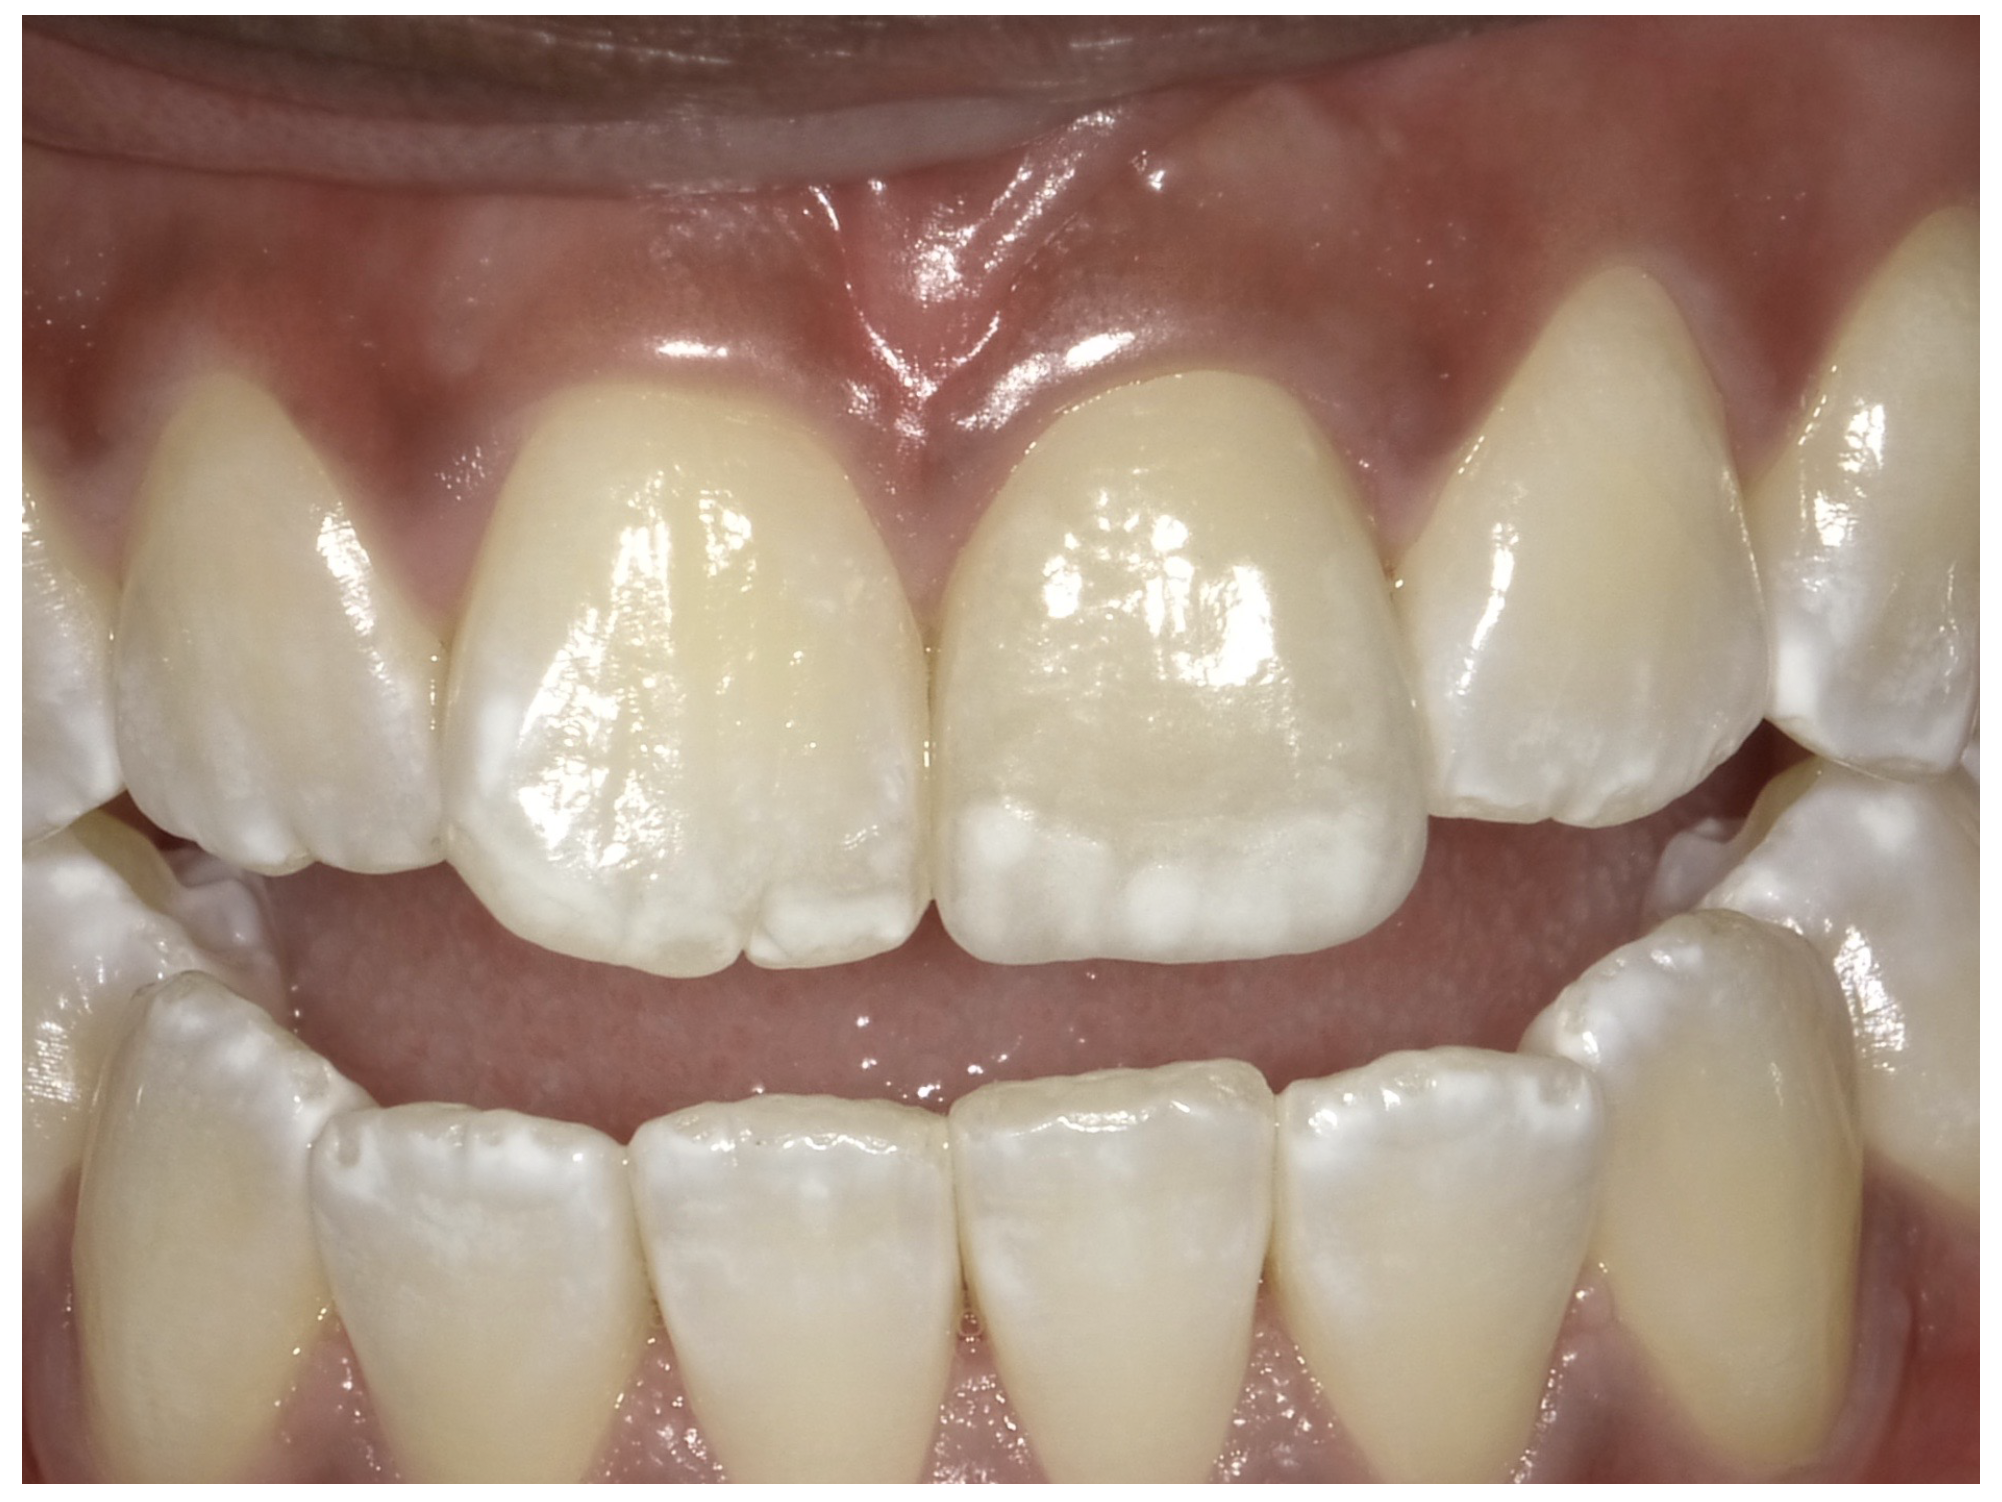

For the case in Figure 9 through Figure 11, the patent presented for an initial consultation with bonding completed on teeth Nos. 7 through 10 a few years prior with a chief complaint of not liking the way the resin bonding looked and how it was wearing. Up to this point, the bonding had repeatedly chipped and been repaired three times already. The patient's canines also exhibited signs of incised wear and flattening, which she did not like. Based on the patient's goals for her smile and her financial budget, she elected to have porcelain veneers completed on teeth Nos. 6 through 11. The total esthetics of the case design were somewhat limited given that the patient's esthetic zone included her posterior teeth and mandibular anterior teeth. Therefore, the color and characteristics of the veneers had to match her existing dentition closely.

In another case, the patient presented with very thick, bulky, over-contoured veneers done on teeth Nos. 7 through 10 when she was a teenager. There also was some recession and staining at the margins (Figure 12). The clinician decided to restore teeth Nos. 6 through 11. A preparation design was required with provisionals removed. As tooth structure could not be regrown, the practitioner made the best of the situation. There was good gum health, which is important for isolation and marginal seal. The clinician cemented with a universal, doing six units at one time. Minimal cleanup was required. At a 1-month follow-up visit, although tissue still was settling in, the contours were natural. After a year (Figure 13), the gum filled in nicely and was in excellent health, and there was good color stability and seamless marginal integrity.